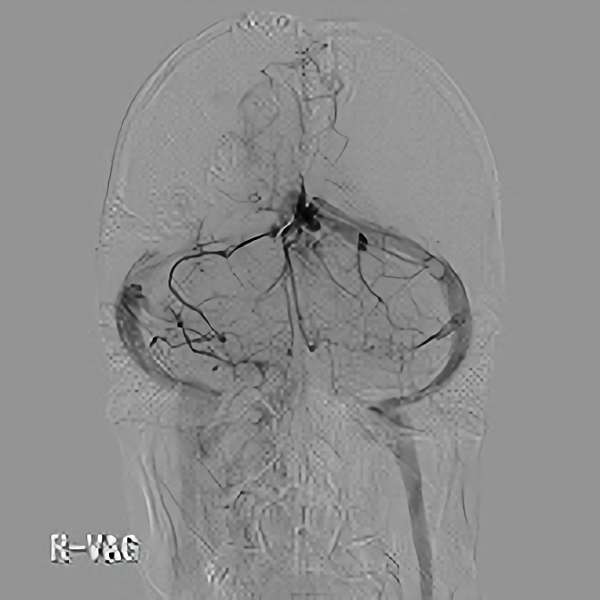

脳血管撮影

手術前

手術後